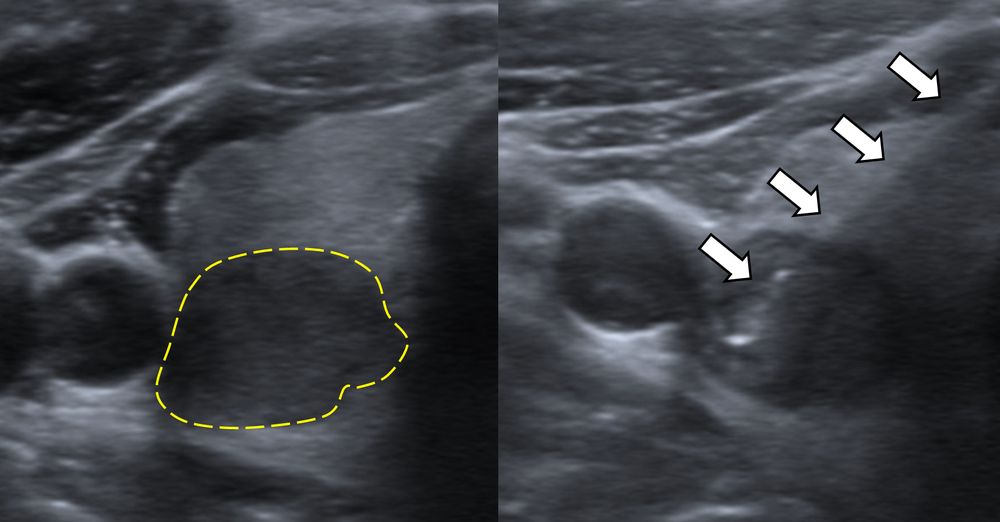

Η διαδερμική βιοψία είναι μία ελάχιστα επεμβατική μέθοδος λήψης υλικού από τον όγκο για κυτταρολογική και ιστολογική εξέταση, από εστιακές αλλοιώσεις του ήπατος, πνεύμονα, νεφρού κλπ. Συστήνεται από τον κλινικό ιατρό ανάλογα με το είδος και το μέγεθος της βλάβης και πραγματοποιείται με ασφάλεια από επεμβατικό ακτινολόγο με την καθοδήγηση αξονικού τομογράφου ή υπερήχων. Στη σύγχρονη ογκολογική θεραπεία όπου γίνεται προσπάθεια καταπολέμησης του καρκίνου σε μοριακό επίπεδο κρίνεται αναγκαία η ακριβής ιστολογική ταυτοποίηση του όγκου ώστε να εφαρμοσθεί εξατομικευμένη θεραπεία για το βέλτιστο αποτέλεσμα. Οι κατευθυνόμενες βιοψίες στοχευουν στο να παρέχουν στον κλινικό ογκολόγο το απαραίτο ιστοπαθολογικό υλικό που θα του επιτρέψει να εφαρμόσει την κατάλληλη θεραπεία για τον ογκολογικό ασθενή.